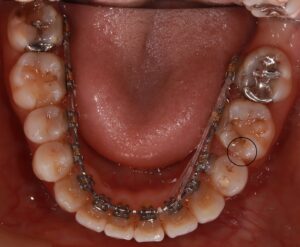

しかし、下の抜歯をしたスペースが順調に埋まってきました。

奥に引っ張られた分、前歯の隙間が少し開いてきたので、次はここも埋まるようにしていきます。